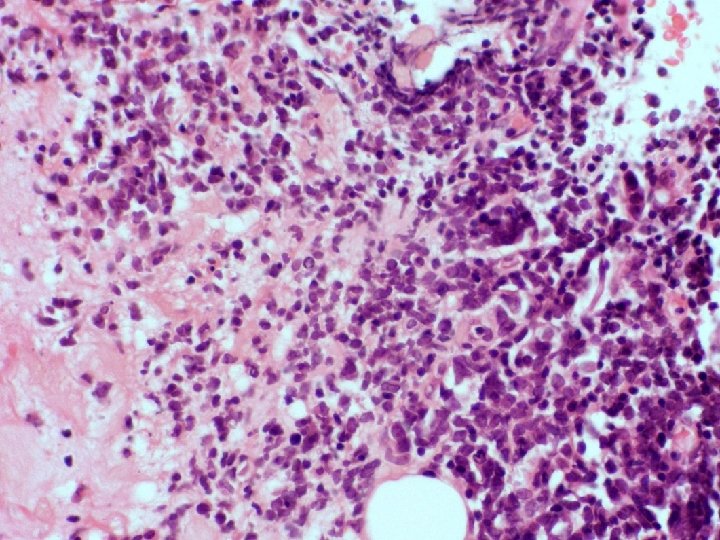

�Case number: 194 �Male aged 88 years. � 2 -3 month history of mass

�Case number: 194 �Male aged 88 years. � 2 -3 month history of mass on left thigh. �TTF-1 negative, CK 7 negative, S 100 negative. �CK 20 positive, Chromogranin positive, CD 56 positive, Synaptophysin positive. �Ellipse of skin 80 x 10 mm with 20 mm depth bearing a pink nodule 15 mm dimension.

�Most popular diagnosis � Merkel cell carcinoma